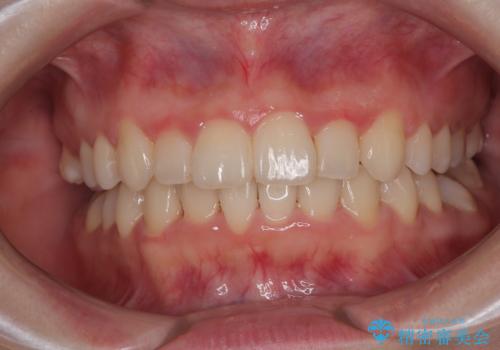

捻れて前に出ている前歯 ワイヤー装置での非抜歯矯正